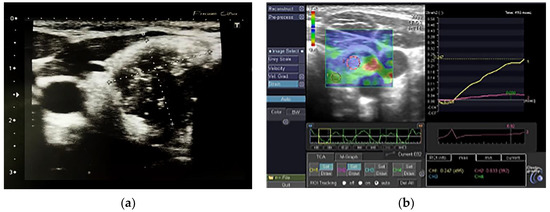

2.3. Thyroid Imaging—Ultrasonography and Elastography